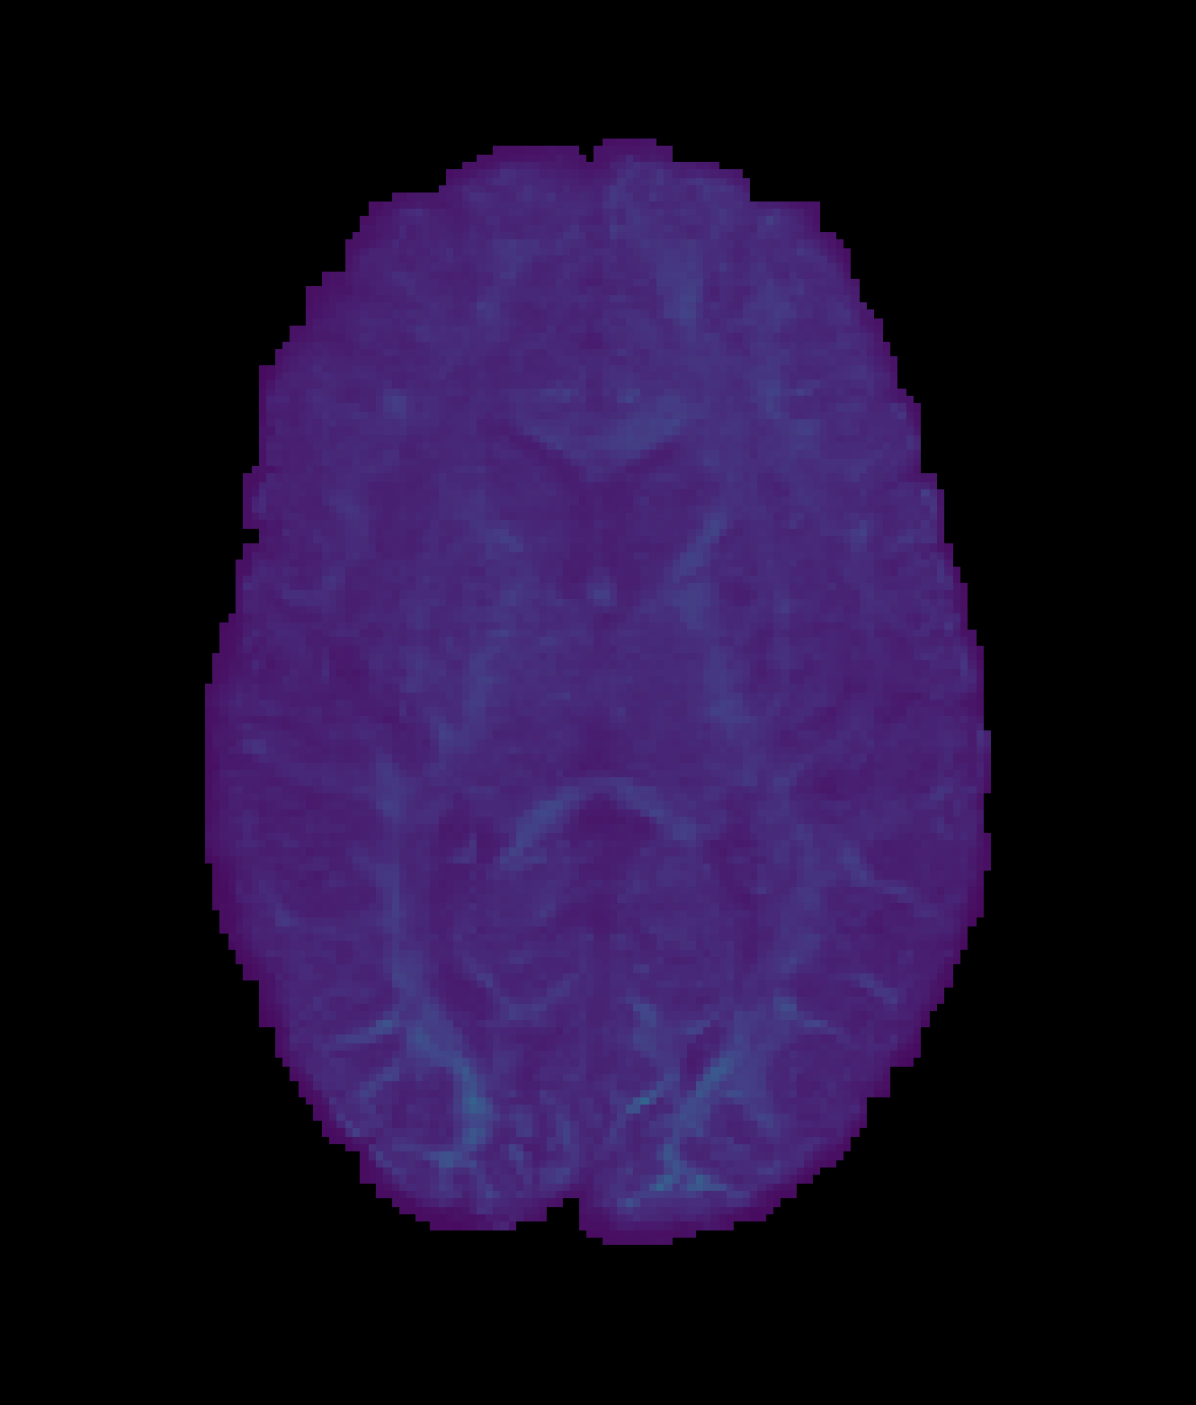

Table 3 summarises the performance in FBA in the low resolution baseline and model based reconstructions compared to the high resolution ground truth, whilst Figure 3 visualises a subset of reconstructed FODs within an axial slice. Here, all PCCNN models performed better than the low resolution baseline in all three sampling schemes in FOD ACC, and had lower AFD AE in the two lowest sampling schemes. The PCCNN models performed competitively against the RCNN. However, in the smallest sub-sampling scheme qin=6subscript𝑞in6q_{\mathrm{in}}=6, or equivalently 6.6%percent6.66.6\% of the original number of voxels, the RCNN performed slightly better. Whilst the low resolution data had lower AFD AE at qin=20subscript𝑞in20q_{\mathrm{in}}=20, the PCCNN models had, in the worse case, a relative increased mean error of approximately 6%percent66\%, compared to 35%percent3535\% increase in the RCNN model. Additionally, the PCCNN models had greater ACC compared to the low resolution baseline across all sub-sampling schemes, suggesting that their use in probabilistic tractography [33] and connectomics [4] would be beneficial.

Refer to caption

(a) ROI

(b) High Resolution

(c) Low Resolution

(d) RCNN

(e) PCCNN-Bv-Sp

Figure 3: Fibre orientation distributions (FOD)s in one ROI slice for a test subject with metrics derived from both input data and inferred data using various models. Models use single-shell data (b=1000s/mm2𝑏1000ssuperscriptmm2b=1000\mathrm{s/mm^{2}}) with angular dimension size qin=10subscript𝑞in10q_{\mathrm{in}}=10 as input, and produce b=1000s/mm2𝑏1000ssuperscriptmm2b=1000\mathrm{s/mm^{2}} inferred data with angular dimension size 808080. Low Resolution denotes FODs derived from single-shell input only.